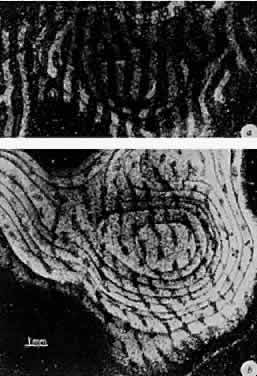

Microelectrode recordings from single cells have demonstrated that most neurons in the visual cortex lose their ability to respond to stimulation of a monocularly deprived eye. Anatomic studies of monocularly lid-sutured animals indicate that the cortical regions that receive axon terminals from geniculocortical neurons driven by the affected eye (constituting its ocular dominance columns) contract while the regions receiving input from the normally experienced eye expand in comparison with normal brains (Fig. 15).72 Other less severe forms of visual deprivation appear to have a considerably less dramatic effect on the architecture of dominance columns.77

Fig. 15. Autoradiographs of monkey visual cortex 2 weeks after injection of a radioactive tracer into the vitreous of one eye. Each figure represents a montage of tangential sections through the cortex. A. Normal monkey. The light stripes, representing labeled eye columns, are separated by gaps of the same width representing the other eye. B. Monocularly deprived monkey, who had the right eye closed at 2 weeks for 18 months. Input from the normal eye is in the form of expanded bands, which in places coalesce, obliterating the narrow gaps that represent the columns connected to the closed eye. (Wiesel TN. Postnatal development of the visual cortex and the influence of environment. Nature 1982;299:583.)